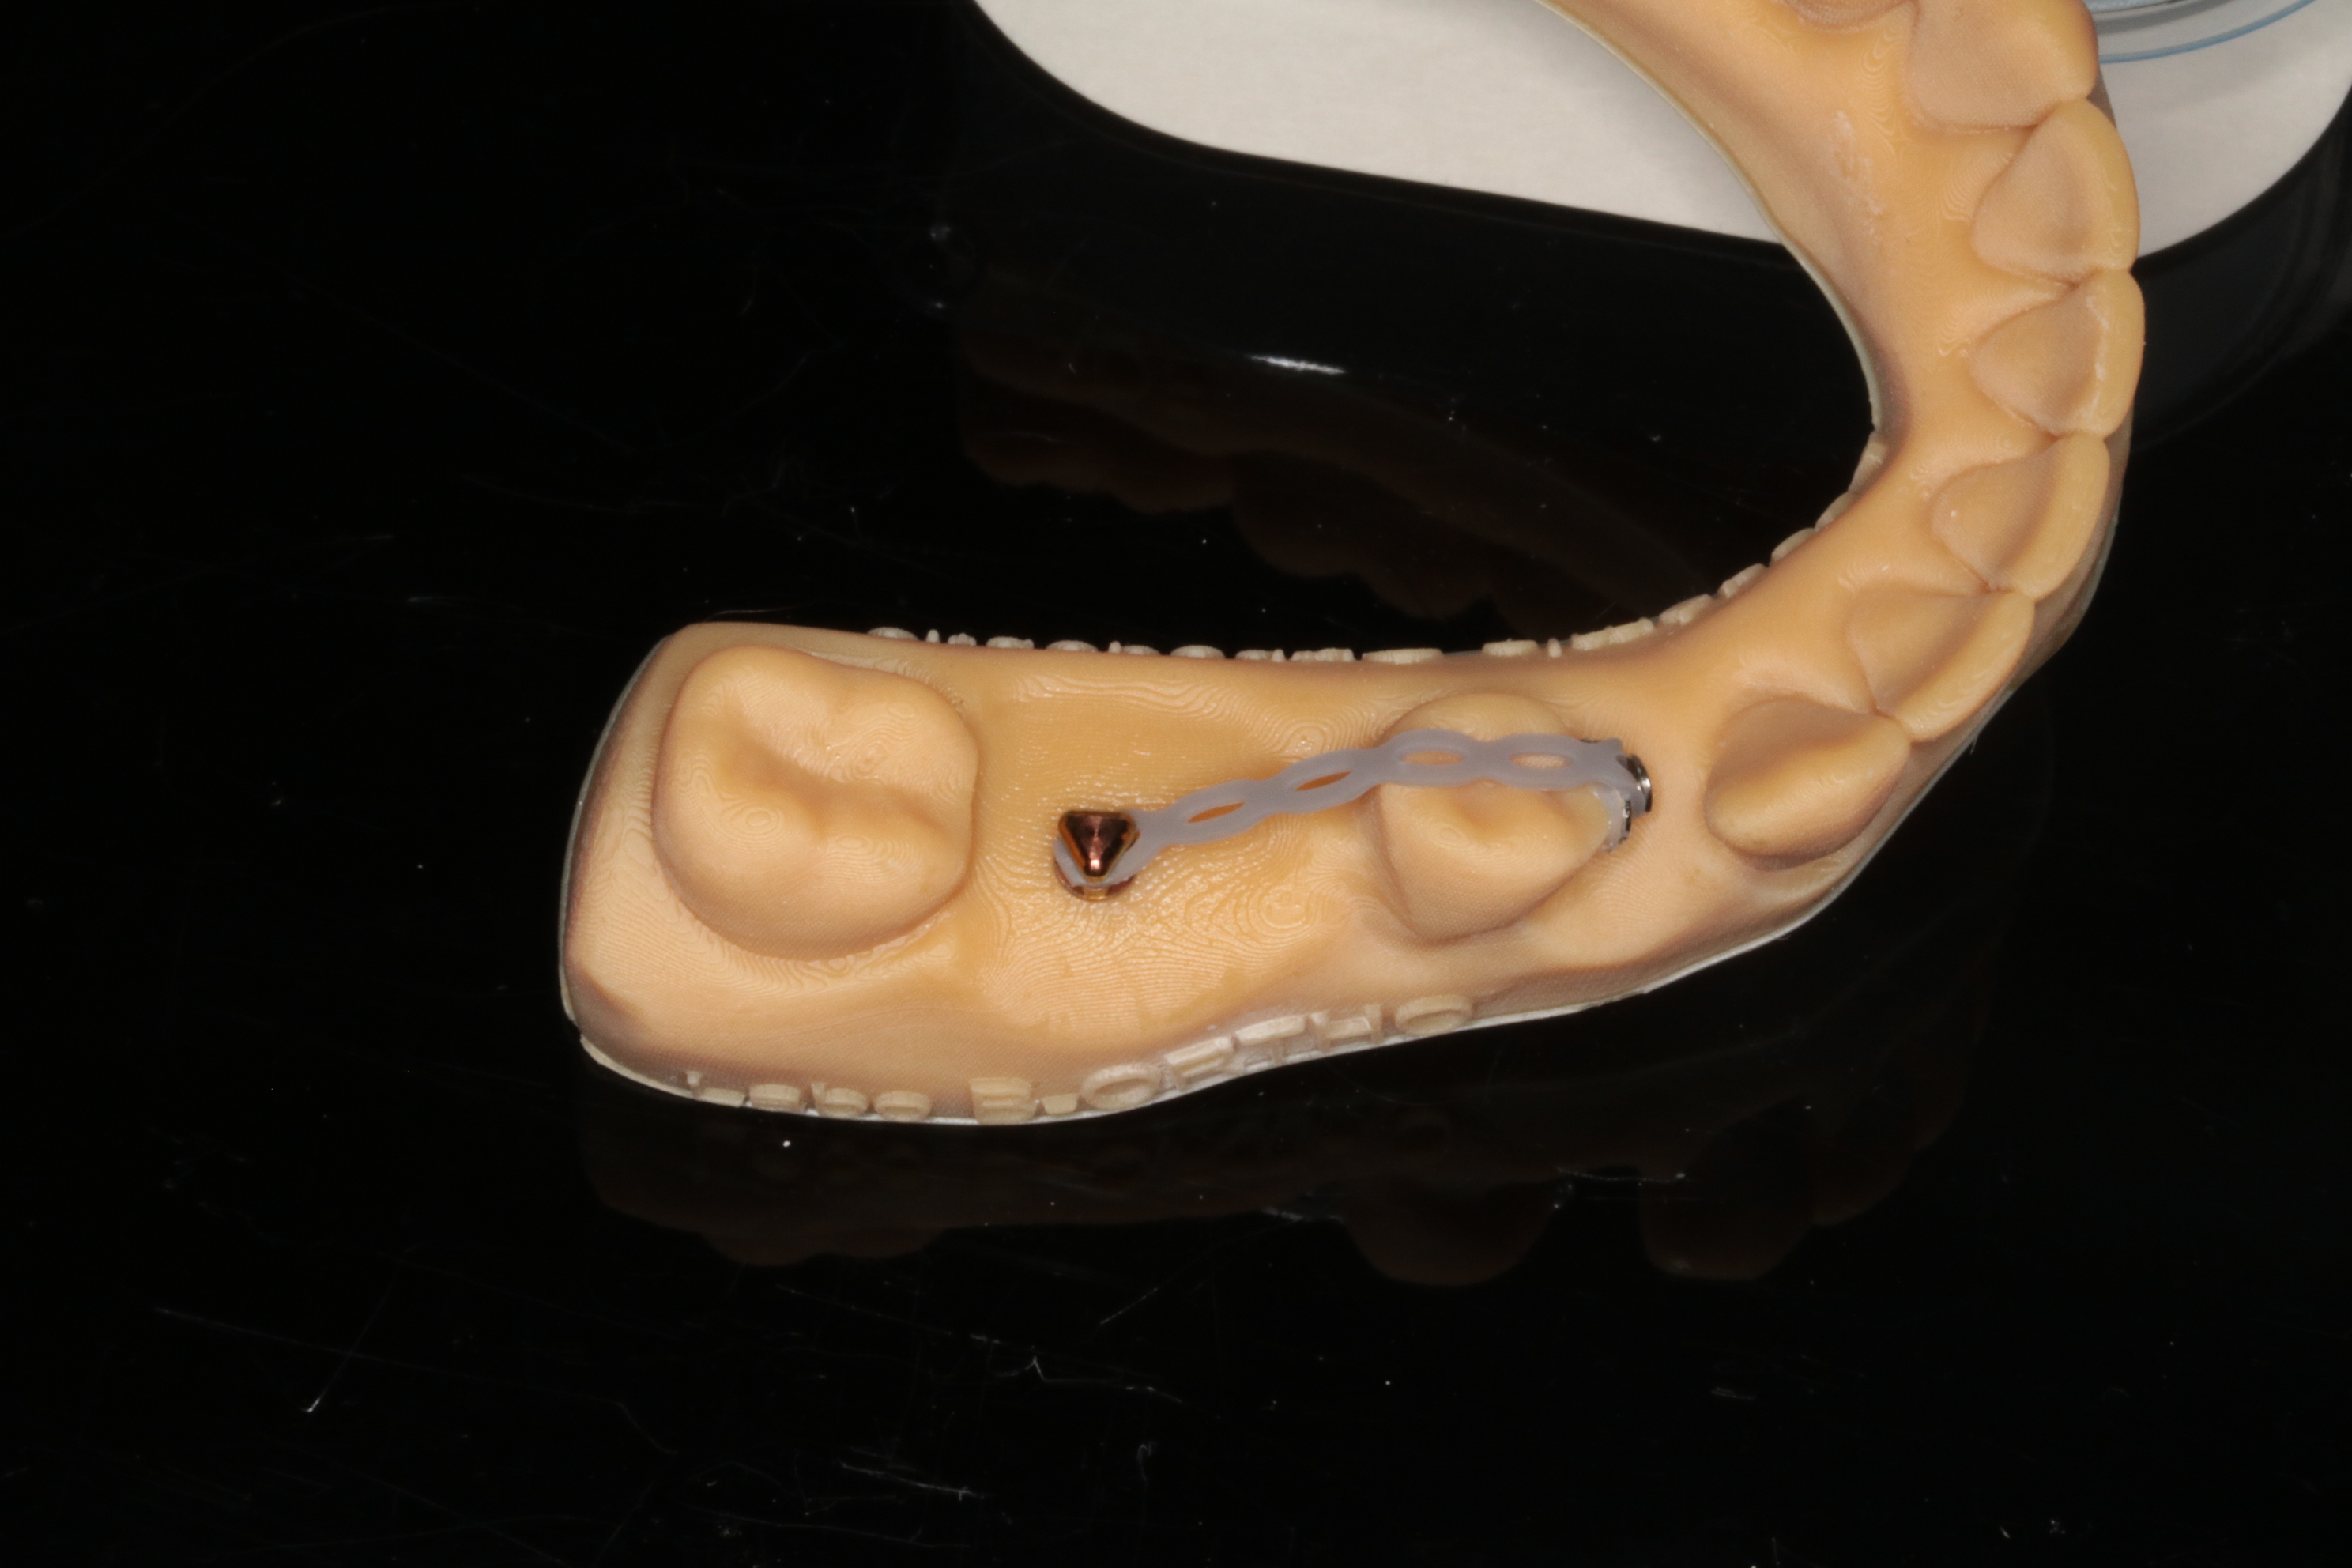

"Les mini vis"

Aix en Provence le lundi 19 janvier 2026

Lors de ce cours réalisé pour l’Académie du Sourire vous pourrez en une journée vous initier à la pose des mini-vis d’ancrage et aux notions simplifiées du déplacement dentaire unitaire.